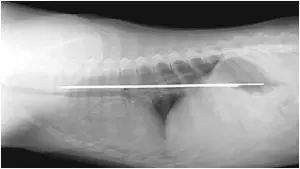

14.在佛罗里达的小狗胃里发现了一个13英寸的刀片,在动手术除去之前,至少已经停留了四天。

在佛罗里达的小狗胃里发现了一个13英寸的刀片,在动手术除去之前,至少已经停留了四天。